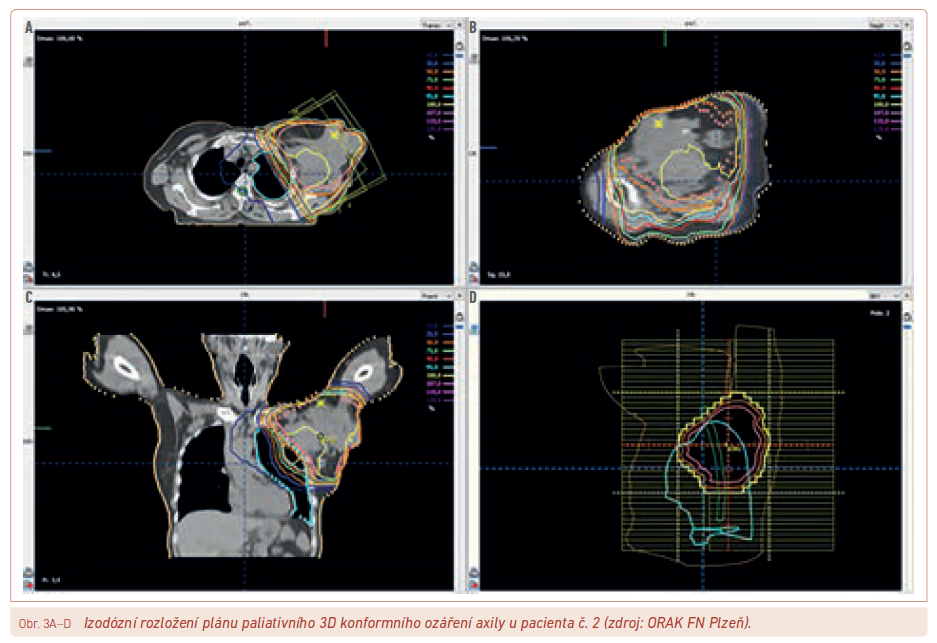

V mnohem častějším paliativním zařazení (např. obr. 3) pak lze použít např. 50 Gy ve 20 frakcích, 40 Gy v 8 frakcích nebo 32 Gy ve 4 frakcích během 4 týdnů i hypofrakcionace zkrácené, např. 30 Gy v 5 nebo 10 frakcích/2 týdny, 20 Gy v 5 frakcích/1 týden, 24–27 Gy ve 3 frakcích za 1–1,5 týdne nebo 8 Gy aplikovaných jednorázově.